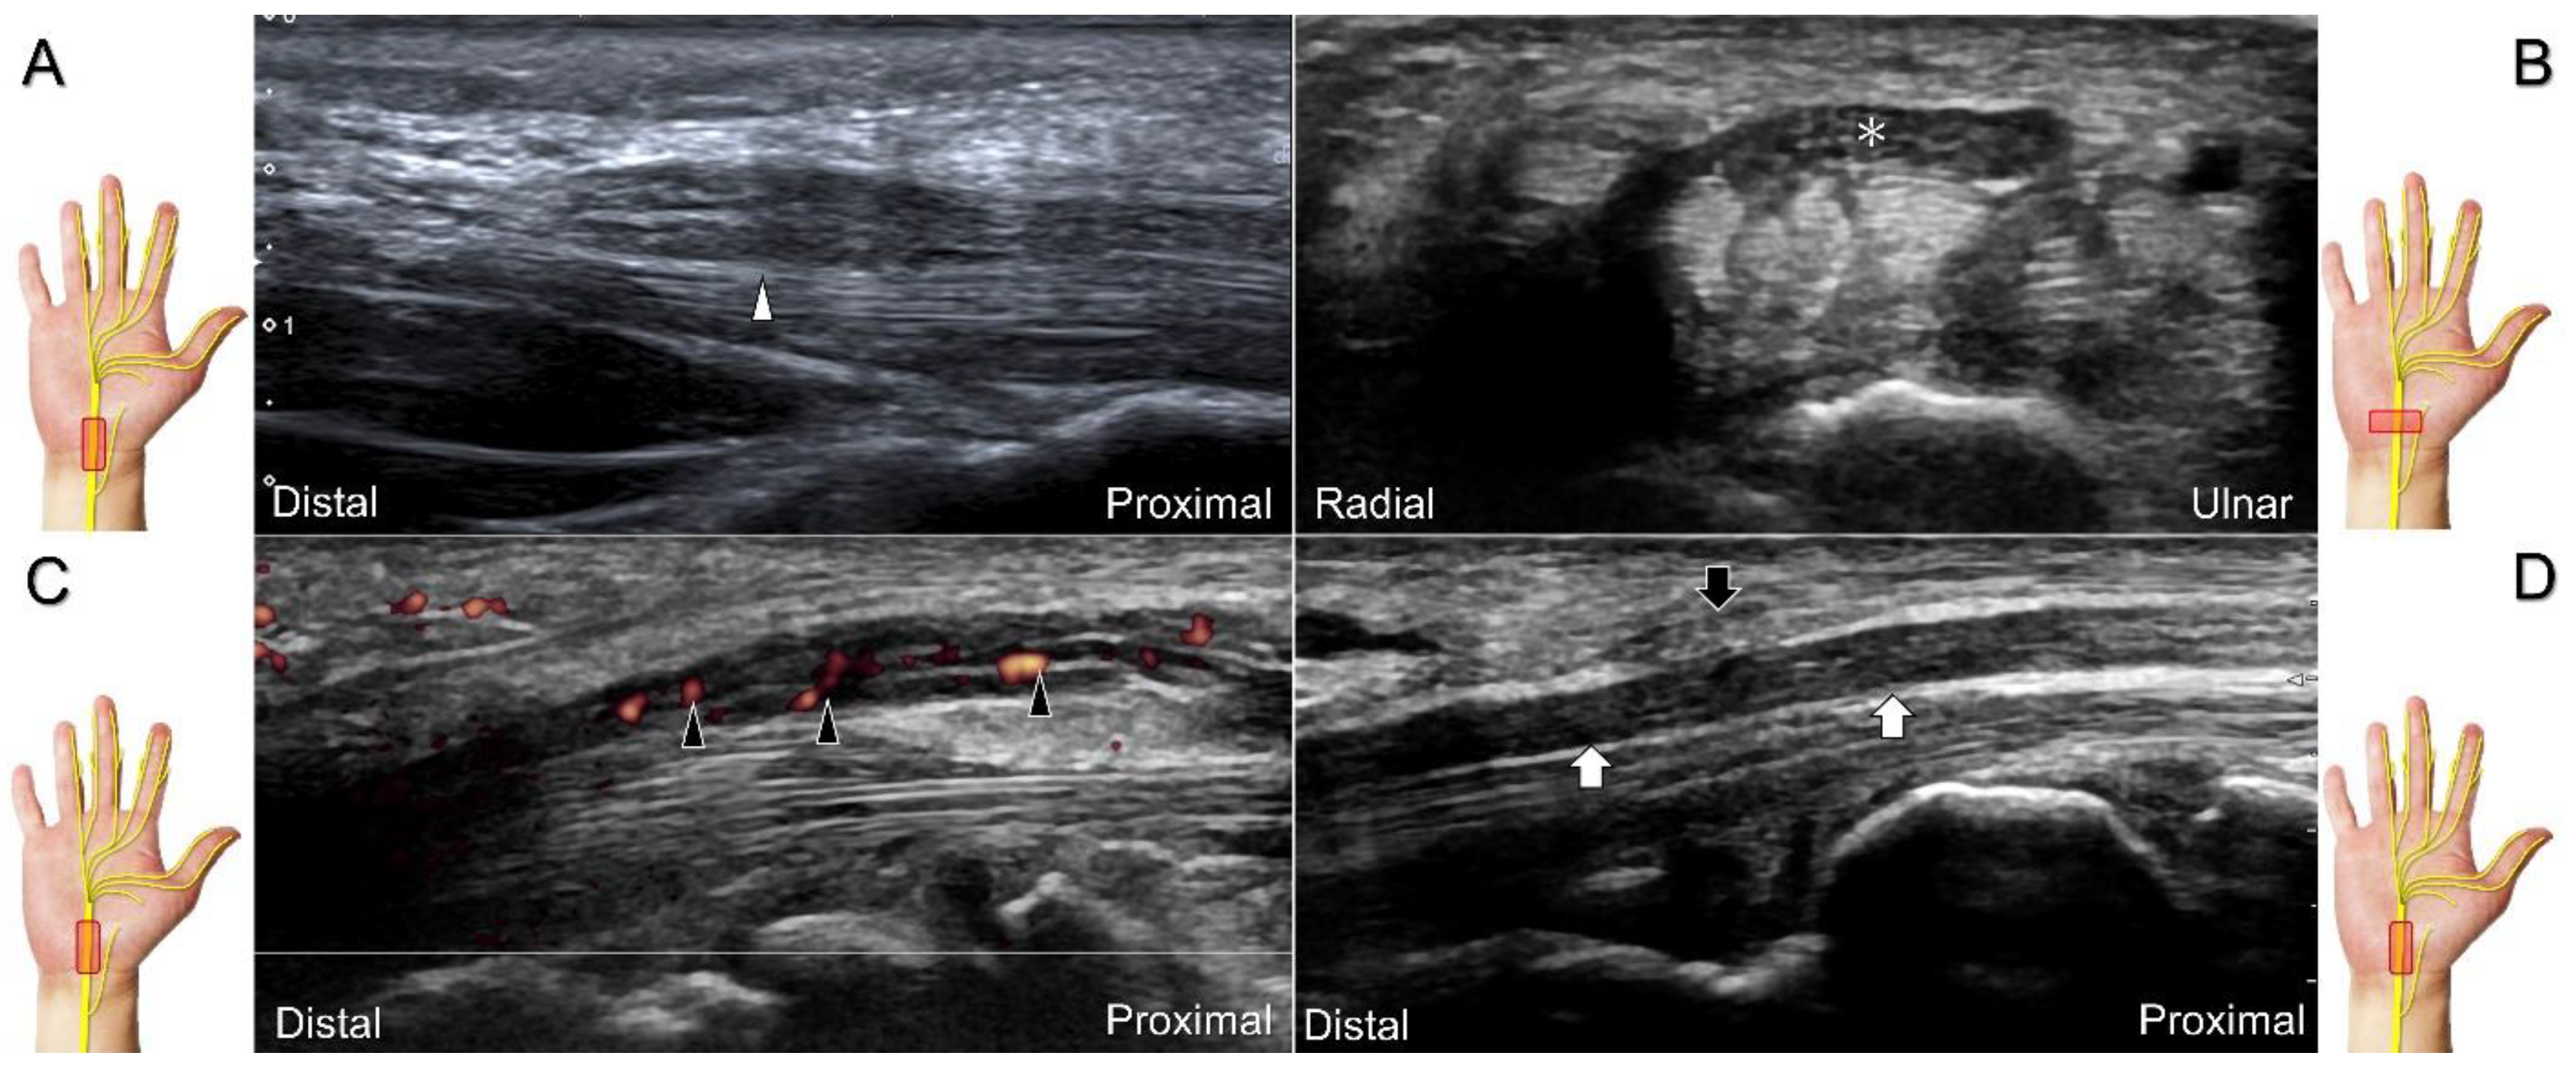

Carpal tunnel syndrome is the most common entrapment neuropathy whereby the median nerve is entrapped by various causes, like hypertrophy of the flexor retinaculum (Figure 2C,D) and compression from the accessory muscles, swollen tendons, ganglions, and bony fractures within the tunnel. Ultrasonographic changes encompass swelling proximal to the entrapment site (Figure 3A), flattening over the entrapment site (Figure 3B), intraneural hypervascularity (Figure 3C), and focal loss of the trimline pattern (Figure 3D).

Figure 3. Sonographic images of patients with carpal tunnel syndrome, showing focal swelling proximal to the compression site (A), flattening at the compression site (B), intraneural hypervascularity (C), and loss of the trimline pattern (D). White arrowhead: focal swelling of the median nerve; asterisk: flattening of the median nerve; black arrowheads: intraneural hypervascularity of the median nerve; white arrows: loss of the trimline pattern of the median nerve; black arrow: thickened flexor retinaculum.